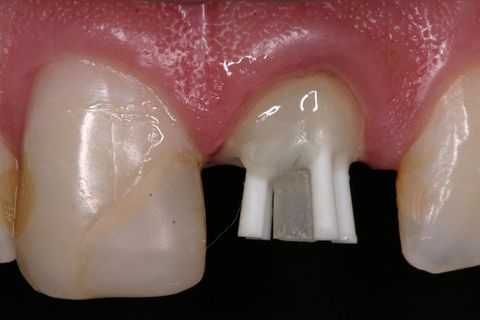

Pino de fibra de vidro #3 (Exacto) pinos acessórios (Reforpin) Angelus, Brasil

Inicialmente, foi removido o tecido cariado do remanescente dental e realizado a seleção do pino de fibra de vidro (Exacto # 3, Angelus, Brasil) e também foram selecionados pinos acessórios (Reforpin, Angelus, Brasil) (Figuras 4).